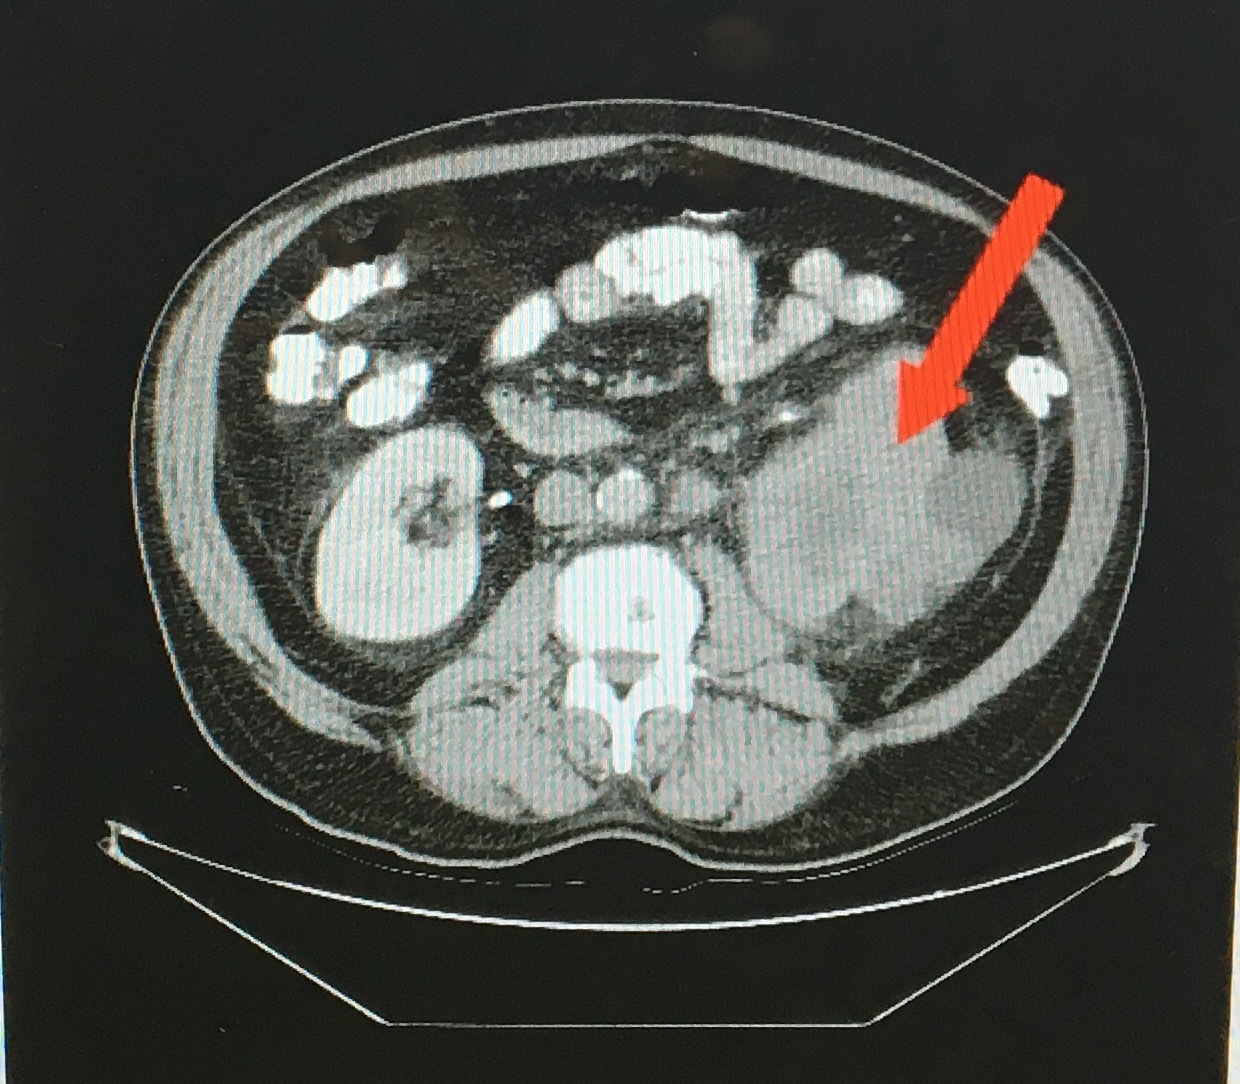

L RCC in image

ADPKD - [Autosomal Dominant Polycystic Kidney Dz]

Describe the Disease - 7

ADPKD

Aneurysm (Berry)

Doomed [HTN and MVP]

[PrOteinuria AND Hematuria]

Kidney Failure (Early vs. Late onset) - Hepatomegaly occurs if cystic involvement

Differentation problem = Etx

Image: Renal Ultrasound which = Dx